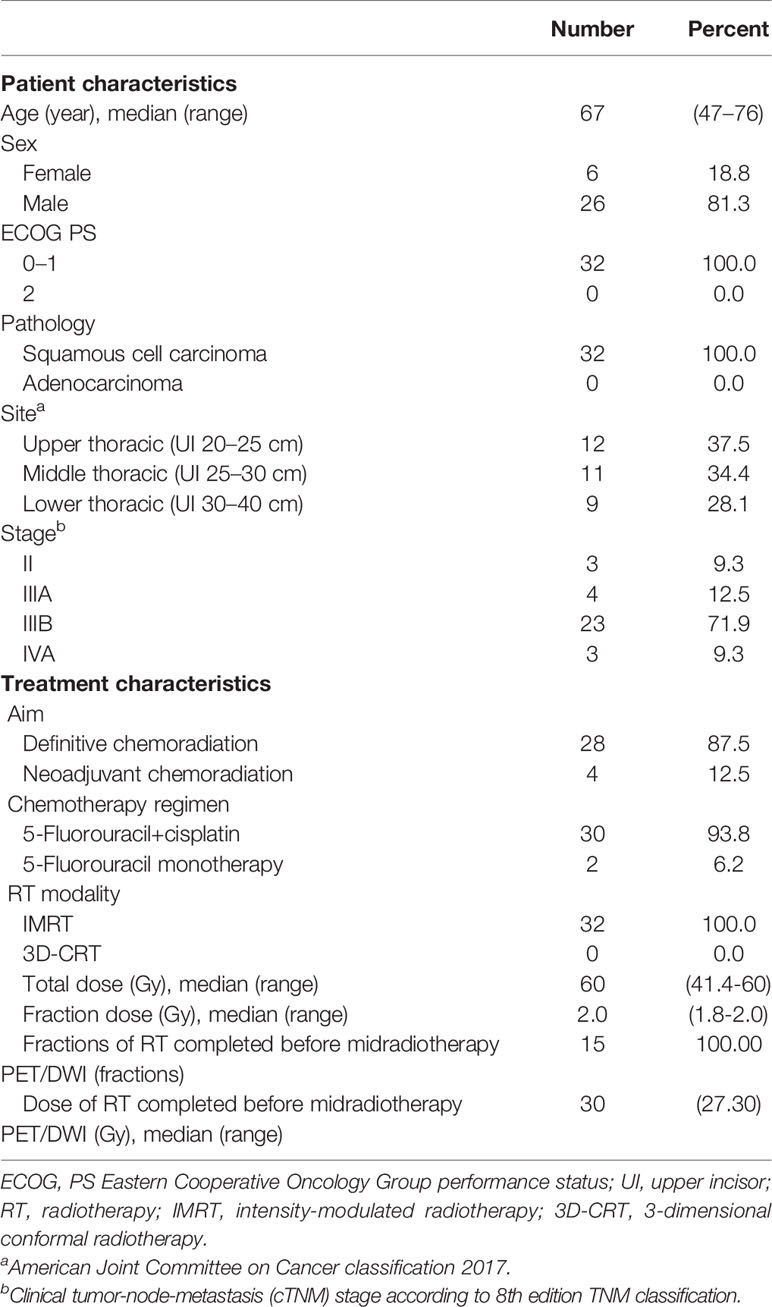

After receiving approval from the local research ethics committee, a total of 35 patients with newly diagnosed, biopsy-proven, nonmetastatic esophageal squamous cancer suitable for concurrent chemoradiotherapy were recruited for this prospective study between November 2016 and May 2020. All patients scheduled to receive neoadjuvant or definitive chemoradiation for EC underwent 3DCT, 18F-FDG PET-CT, and MRI simulation scanning prior to the initiation of RT and after 15 fractions of RT. Written informed consent was obtained from every patient included in this study. Patients were excluded if either pre-RT 18F-FDG PET-CT or DW-MRI data were not available (n = 1), the volume of the tumor on baseline metabolic imaging was extremely small (≤1 cm3) (n = 1), or they did not complete RT (n = 1). Consequently, image data of 32 patients were available for analysis. Patient and treatment characteristics are presented in Table 1.

The volume of GTVCTpre was 26.34 (4.50–118.71) cm3, leading to a significantly positive correlation with both GTVPETpre (Figure 1A) and GTVDWIpre (Figure 1D) (r = 0.763 and r = 0.809, both p < 0.001). The volume of GTVCTdur was 16.74 (2.92–57.13) cm3 and exhibited a significant positive correlation with both GTVPETdur (Figure 1B) and GTVDWIdur (Figure 1E) (r = 0.826 and r = 0.703, both p< 0.001). Similarly, the relative changes in the volume of PET-CT and DW-MRI (∆GTVPET, ∆GTVDWI) before and during RT demonstrated a significantly positive correlation with that of CT (∆GTVCT) before and during RT (r = 0.616 and r = 0.716, both p < 0.001) (Figure 1).

Figure 1 Scatter plots of correlation between the target volume delineated on18F-FDG PET–CT (GTVPET) and DW-MRI (GTVDWI) and on the corresponding CT (GTVCT) before and during radiotherapy. The best-fit line is shown as the solid line for each scatterplot. (A) GTVPETpre versus GTVCTpre; (B) GTVPETdur versus GTVCTdur; (C) ΔGTVPET versus ΔGTVCT; (D) GTVDWIpre versus GTVCTpre; (E) GTVDWIdur versus GTVCTdur; (F) ΔGTVDWI versus ΔGTVCT.